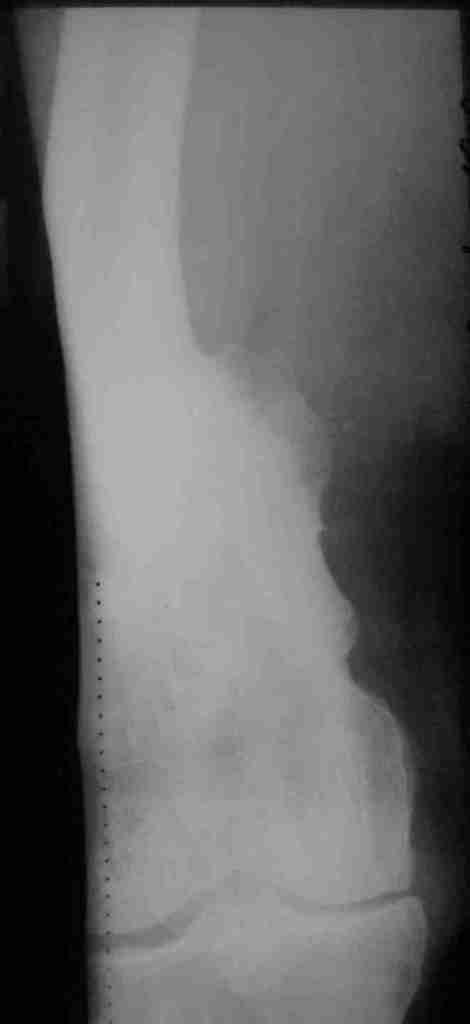

Укорочение правого бедра

Пациент 69 лет. лечился по поводу перелома н/3 левого бедра много лет назад: несостоятельность внутреннего синтеза - АВф- хр. остеомиелит, свищевая форма с периодическими рецидивами.

Результат - укорочение левого бедра 8 см.

Спасибо.В приложении рентгенограммы и внешний вид бедра.